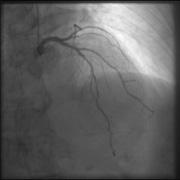

The top image is enhanced using GOPView iRVUltra. The bottom is the original image.

GOPView iRVUltra is a real-time image enhancement filter. The company’s algorithm can define the movements between the images, frame by frame, pixel by pixel, to find structures and orientation for interventional procedures in real-time and without time gaps.

“Interventional radiologists always look to strike an ideal balance between the required image quality and the radiation dose for any given procedure,” Tollstadius said. “As a result, they rely heavily on the newest advancements in image quality enhancement and dose reduction technologies. Generally, it takes an increased dose to enhance the image quality. With the GOPView iRVUltra, radiologists no longer have to compromise, as superior image quality can be achieved despite low-dose images.”